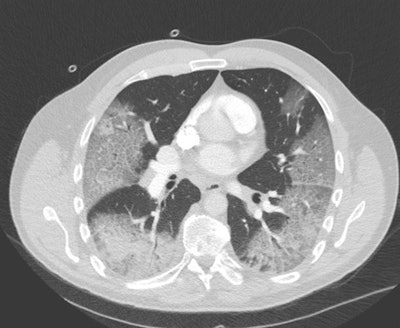

"COVID-19 causes a wide variety of findings on these scans, most typically ground-glass type of densities located on the outside of both lungs (see white areas in figure)," he continued. "The accuracy of chest CT to diagnose COVID-19 has been reported as high and can predate a positive classic serological RT-PCR test. Therefore, in endemic areas where the healthcare system is under pressure, hospitals with a high volume of admissions are using CT for rapid triage of patients."

There is a role for chest CT to assess COVID-19 infection in patients with severe and worsening respiratory disorders. Based on the images, doctors can evaluate how severely the lungs are affected and how the patient's disease is evolving, which is helpful in making treatment decisions, according to Ranschaert.